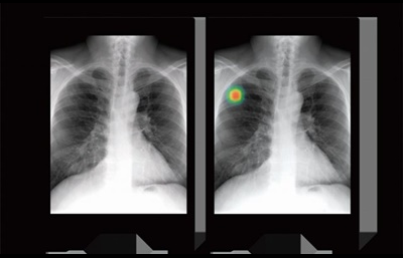

이번 기사에서는 폐암 초기 증상에 대해 자세히 정리해 알려 드리겠습니다 . 폐암은 국내암 사망률 1 위로, 과거에는 흡연이 폐암의 주된 원인 이었지만 , 현재는 비흡연 폐암 환자도 대폭 증가했습니다 . 폐암은 의학 기술로 발달하여 생존율이 높아지고 있습니다 . 폐암의 초기 증상은 무엇인가를 알아보겠습니다.

폐암의 초기 증상